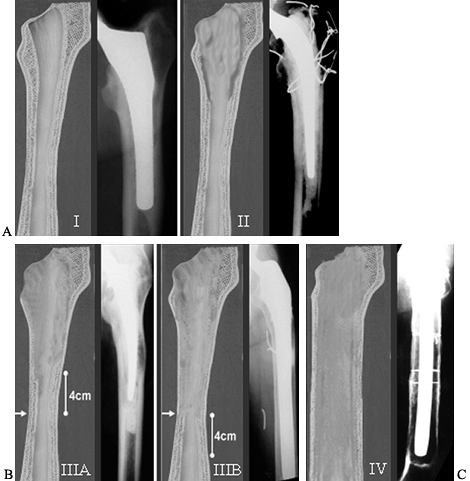

Figure 106.20. Paprosky classification of acetabular defects: (A) type 1, minimal damage; (B)

type 2A–C, increased destruction but greater than 50% host bone available for uncemented cup fixation. Head center has migrated superiorly less than 3 cm; (C) radiograph demonstrating a type 2A defect; (D) type 3A defect, more extensive destruction, with greater than 3 cm superior migration of the head center. (E) type 3B defect, major pelvic destruction with superior and medial migration and greater than 3 cm head center migration, less than 50% host bone available for reconstruction. |

major types with five subtypes by evaluation of these four radiographic

landmarks (Table 106.10; Fig. 106.20).

and 2 may have large cavitary defects but can be treated with an

uncemented cup because the defects are contained and the supporting rim

of the acetabulum is largely intact. The type 3 defects include large

cavitary and segmental

defects,

effectively becoming partially uncontained cavitary defects. In this

situation, an uncemented cup depends on sufficient host bone for

stability. This is not always available, necessitating the use of cages

and allografts. In the type 3B acetabulum, the host bone cannot be

relied on and must be supplemented with either cancellous or structural

grafts.